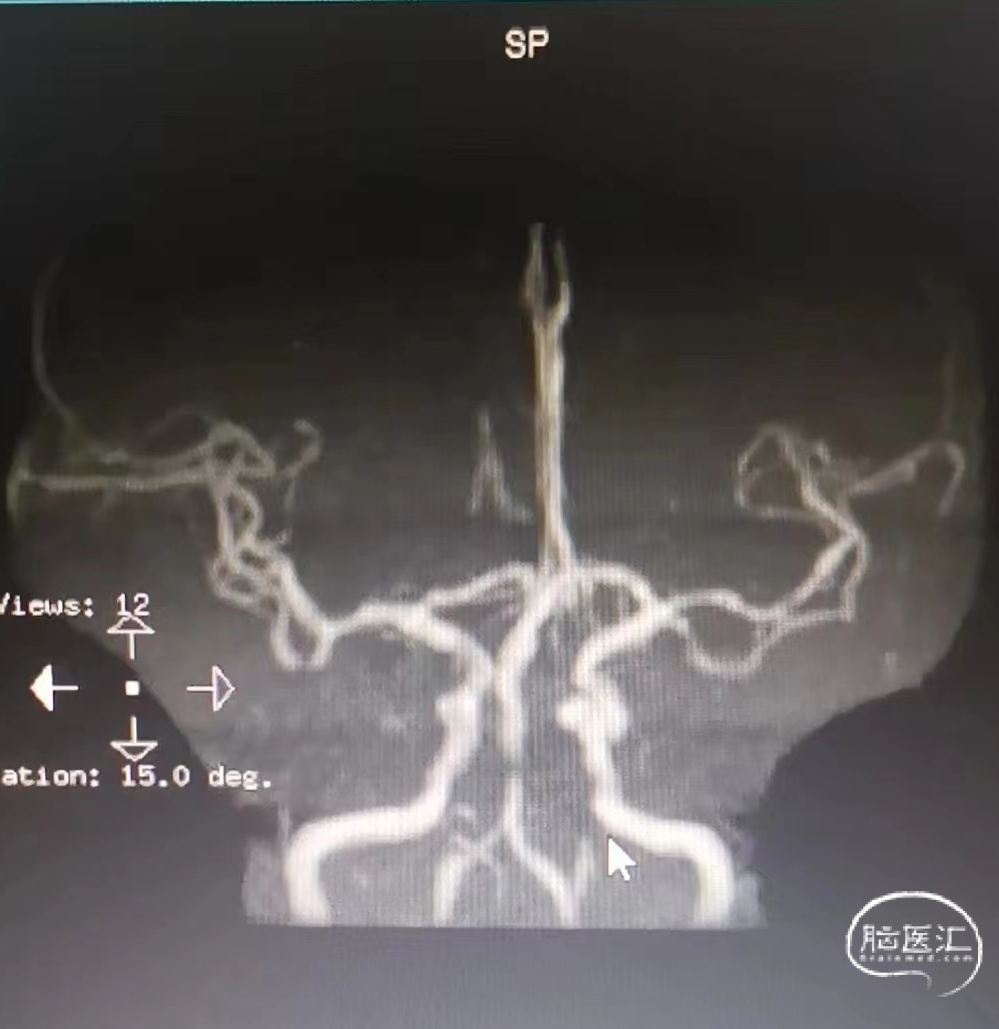

头颈部CTA:头颈部动脉粥样硬化,右侧椎动脉颅内段及两侧大脑后动脉重度狭窄,基底动脉闭塞。